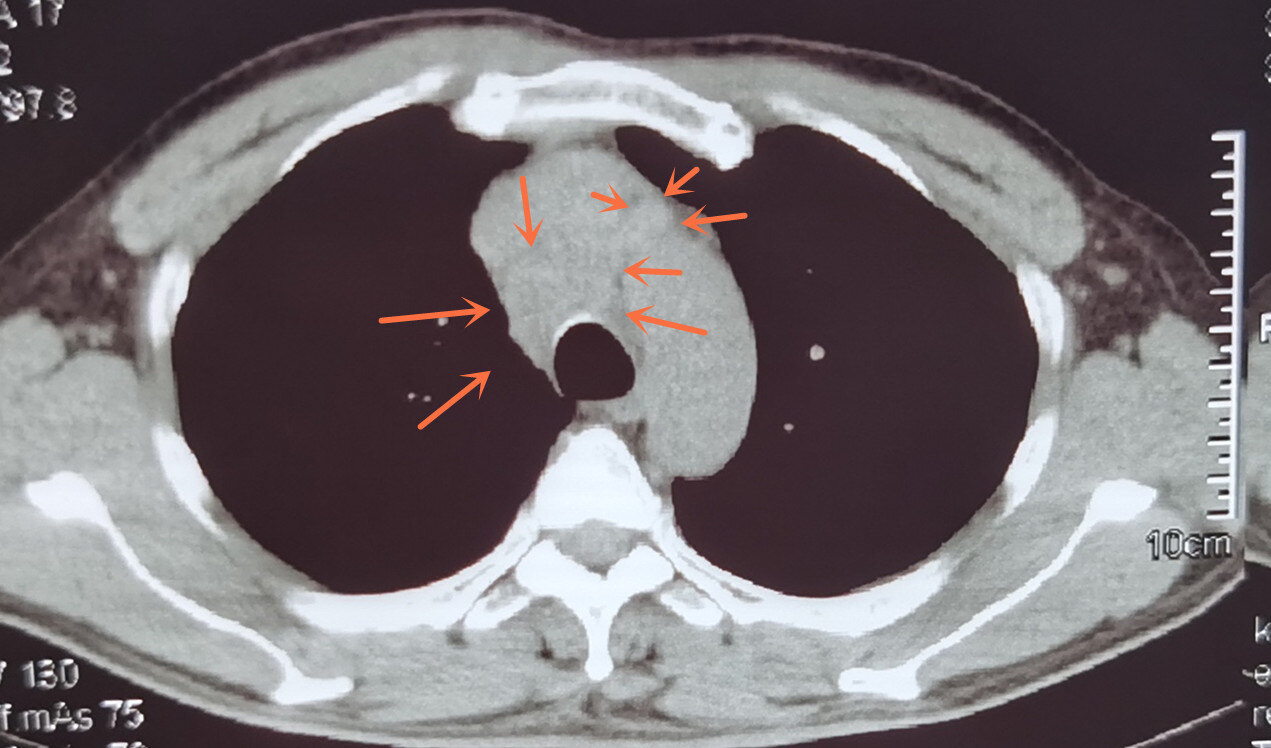

纵隔淋巴结转移.jpg

肺癌纵隔淋巴结转移研究进展 new.doc